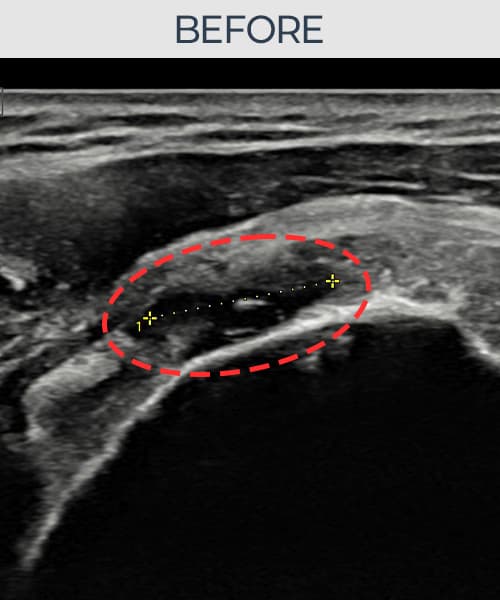

治療実績 — 超音波エビデンス

実際の患者様の施術前後の超音波画像。

手術なしで実現できる回復をご確認ください。

[経過期間: 23.07.18~23.09.14]

[縫縮術] 超音波検査にて左 棘上筋腱 광범위 部分断裂(15mm × 6mm (腱厚の約70%欠損))を確認。縫縮術施行後、腱の連続性が回復し、日常生活に復帰されました。